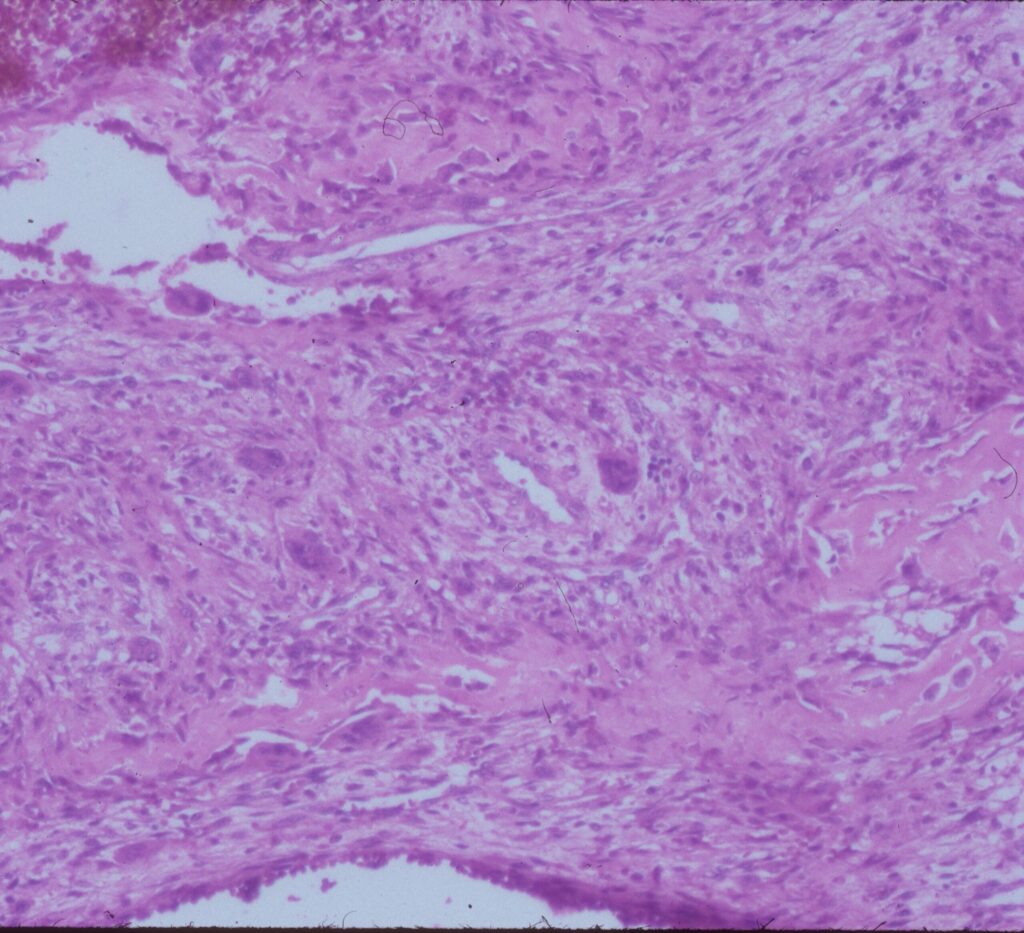

Microscopic Pathology

- Hemorrhagic tissue with large cavitary spaces divided by septum of spindle fibroblastic cells, inflammatory cells and few giant cells.

- Osteoid formation could be noted (reactive and benign in nature)

Fig 3 a,b,c. Microscopic pathology of an Aneurysmal Bone Cyst (ABC):

Figure 3a: There is a large blood filled cystic cavity surrounded by a fibrous septae that includes benign appearing spindle cells, fibrous extracellular matrix and scattered giant cells. There are areas of reactive bone formation. The fibroblastic cells are bland appearing. There are no abnormal mitotic figures.

Fig 3b: Intermediate power of a septum of an ABC: There is no epithelial lining around the wall of the cavity filled with blood. There are spindle cells and scattered giant cells.